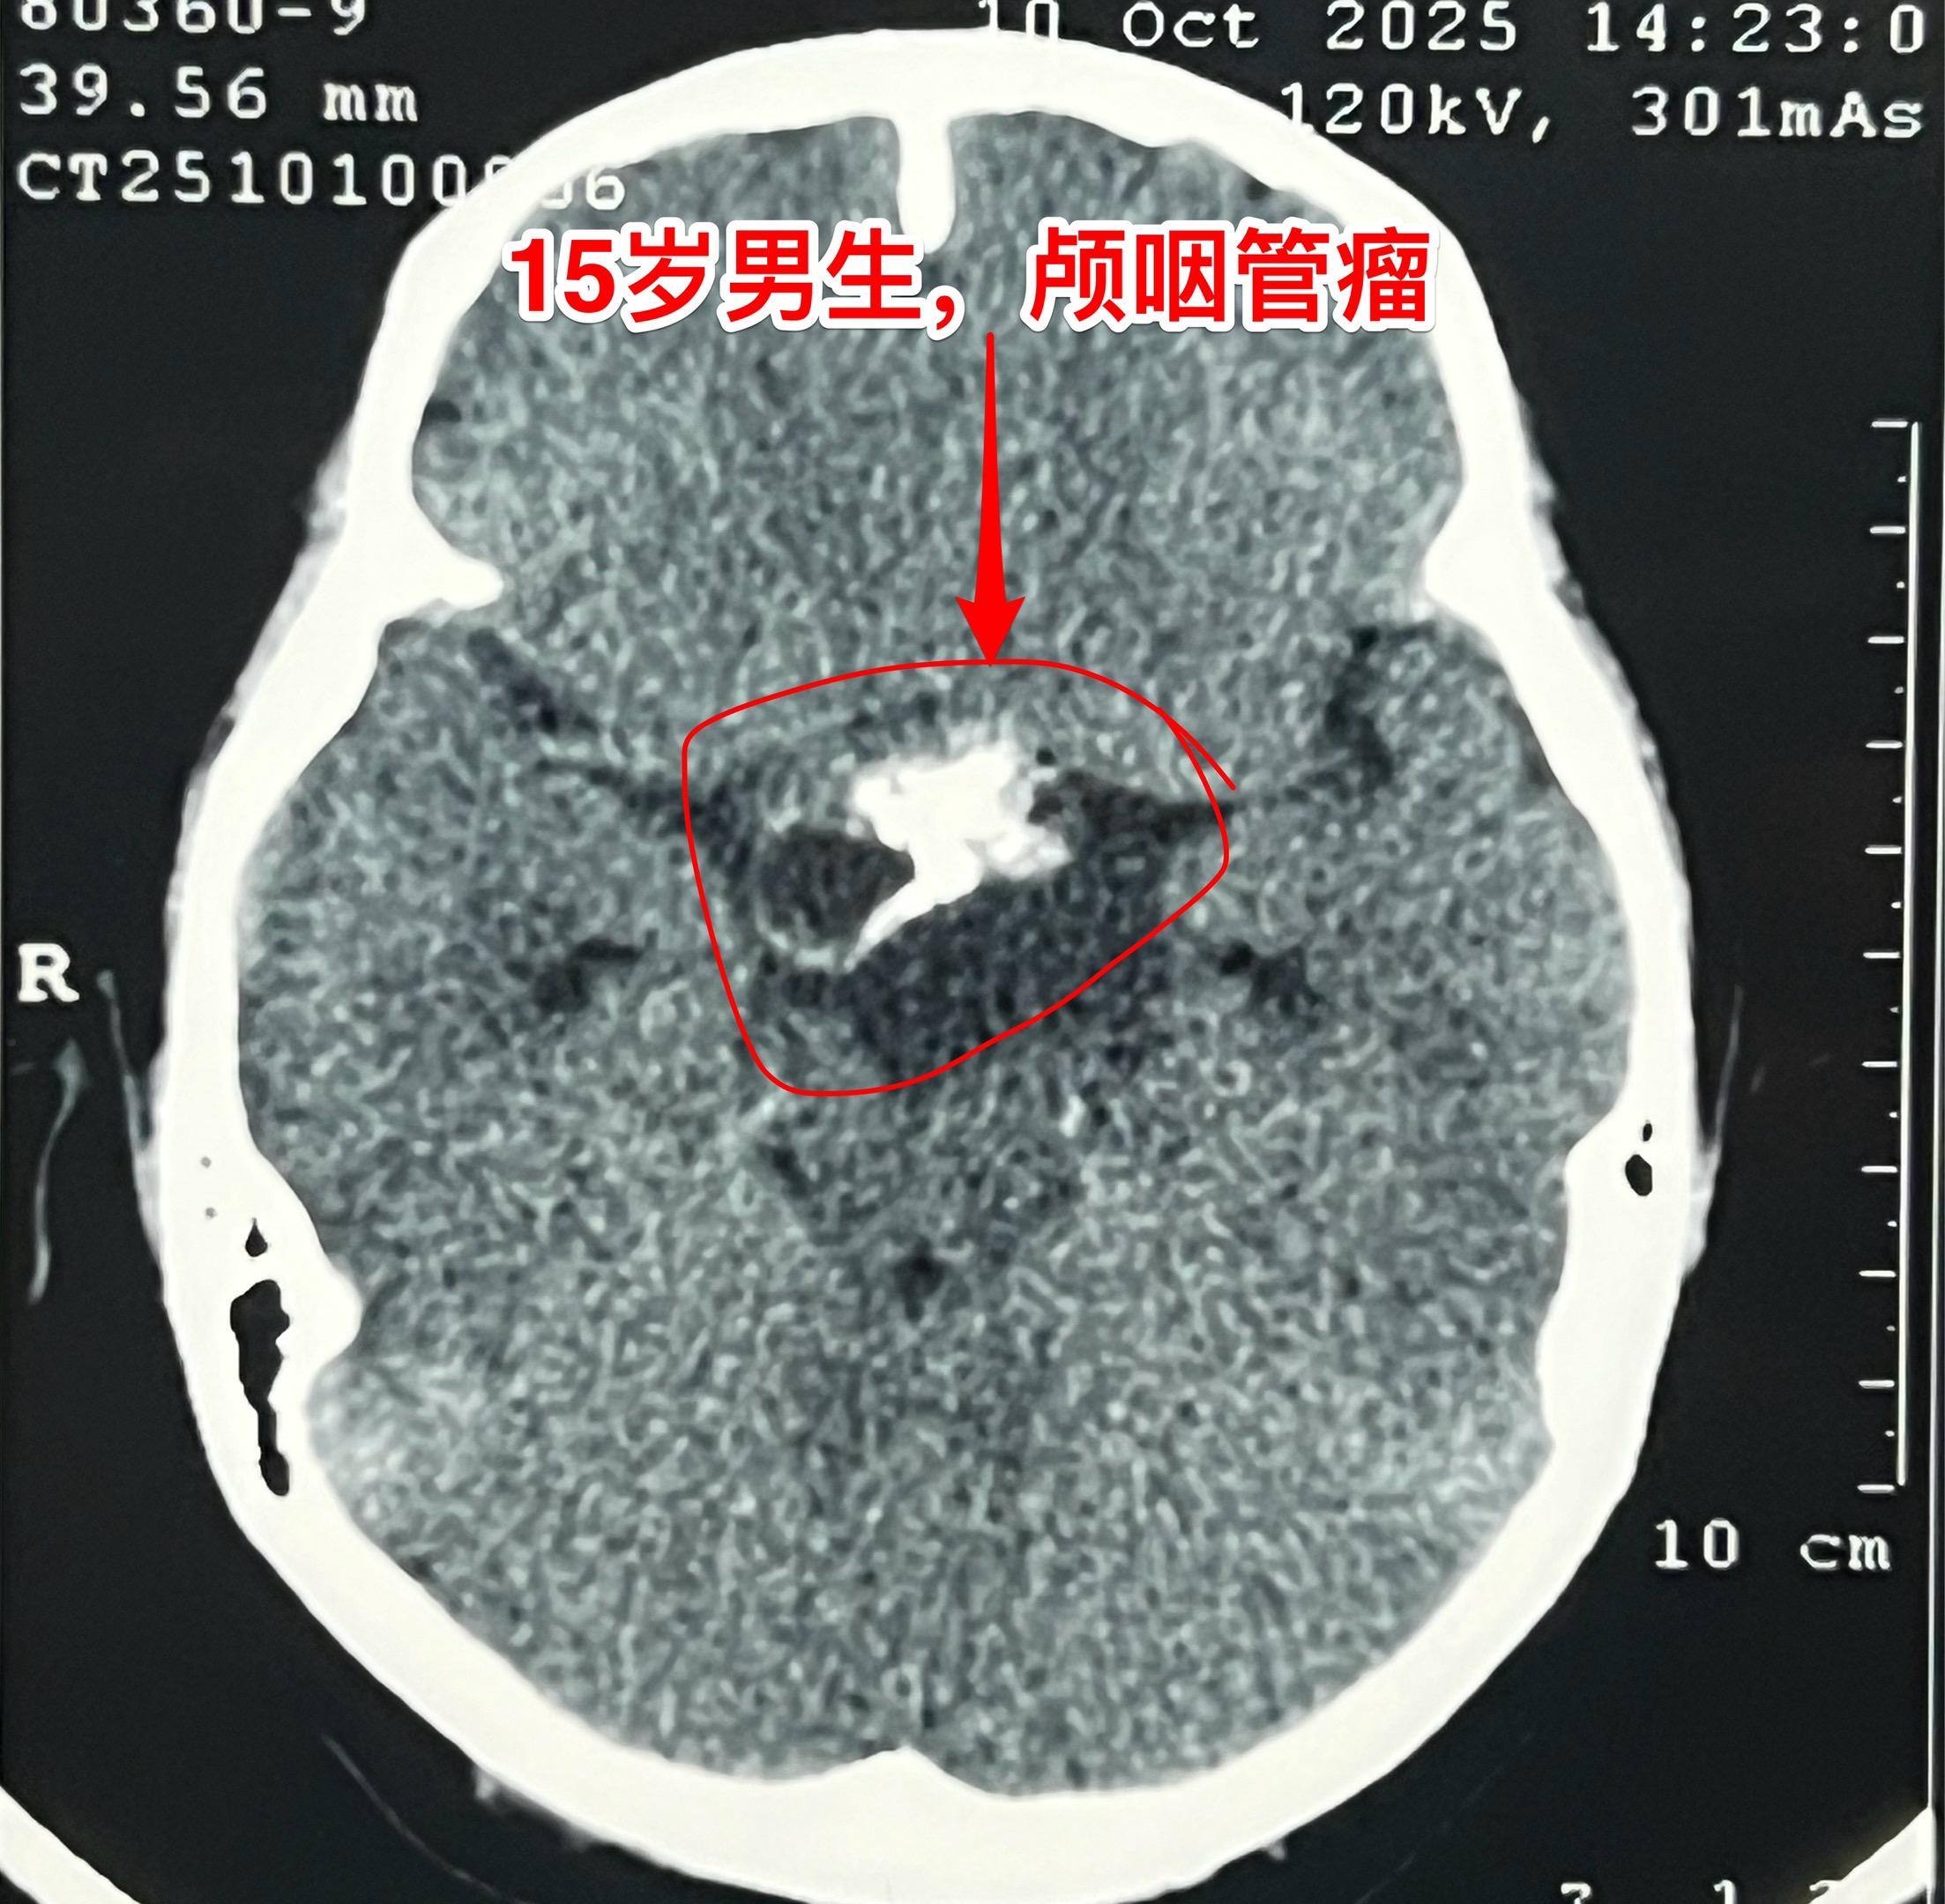

周日加班完成两台颅咽管瘤手术(第167)2025年10月26日(周日)完成了今年的第167例、168例颅咽管瘤手术。 第167例病人,59岁男性,甘肃省武威市人,因视力下降、思维糊涂到医院检查发现颅咽管瘤。 第168例颅咽管瘤患者是15岁的男生,江西省南昌市人,有头痛症状、视力下降症状,但是并未就医。偶然因骑自行车与别人相撞,到医院作头部CT才发现了这个颅咽管瘤。 这两个手术都不简单,肿瘤位置稍有不同,颅咽管瘤均得到完全切除。今天看见两个病人的精神状态均好!